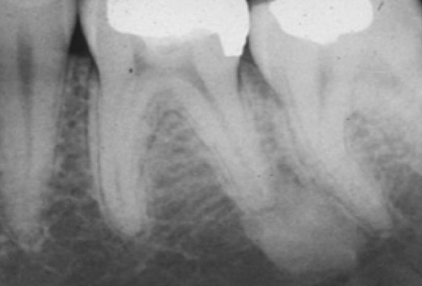

Radiographic Adjacent Structures : radiolucent lesion that extends between the roots, as seen in a traumatic bone cyst (TBC)

scalloping